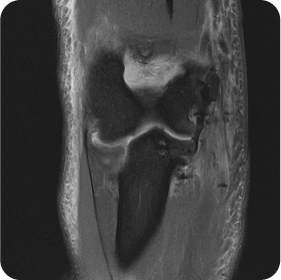

팔꿈치 우측 요골두 인공관절 치환술

수술 전

수술 후